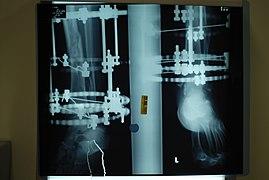

The following case study illustrates the Ilizarov apparatus treatment procedure for a fractured limb. The photographs are of the same patient during the course of treatment.

X-Ray of fracture and initial external fixator applied within 24 hours of patient's admission to hospital